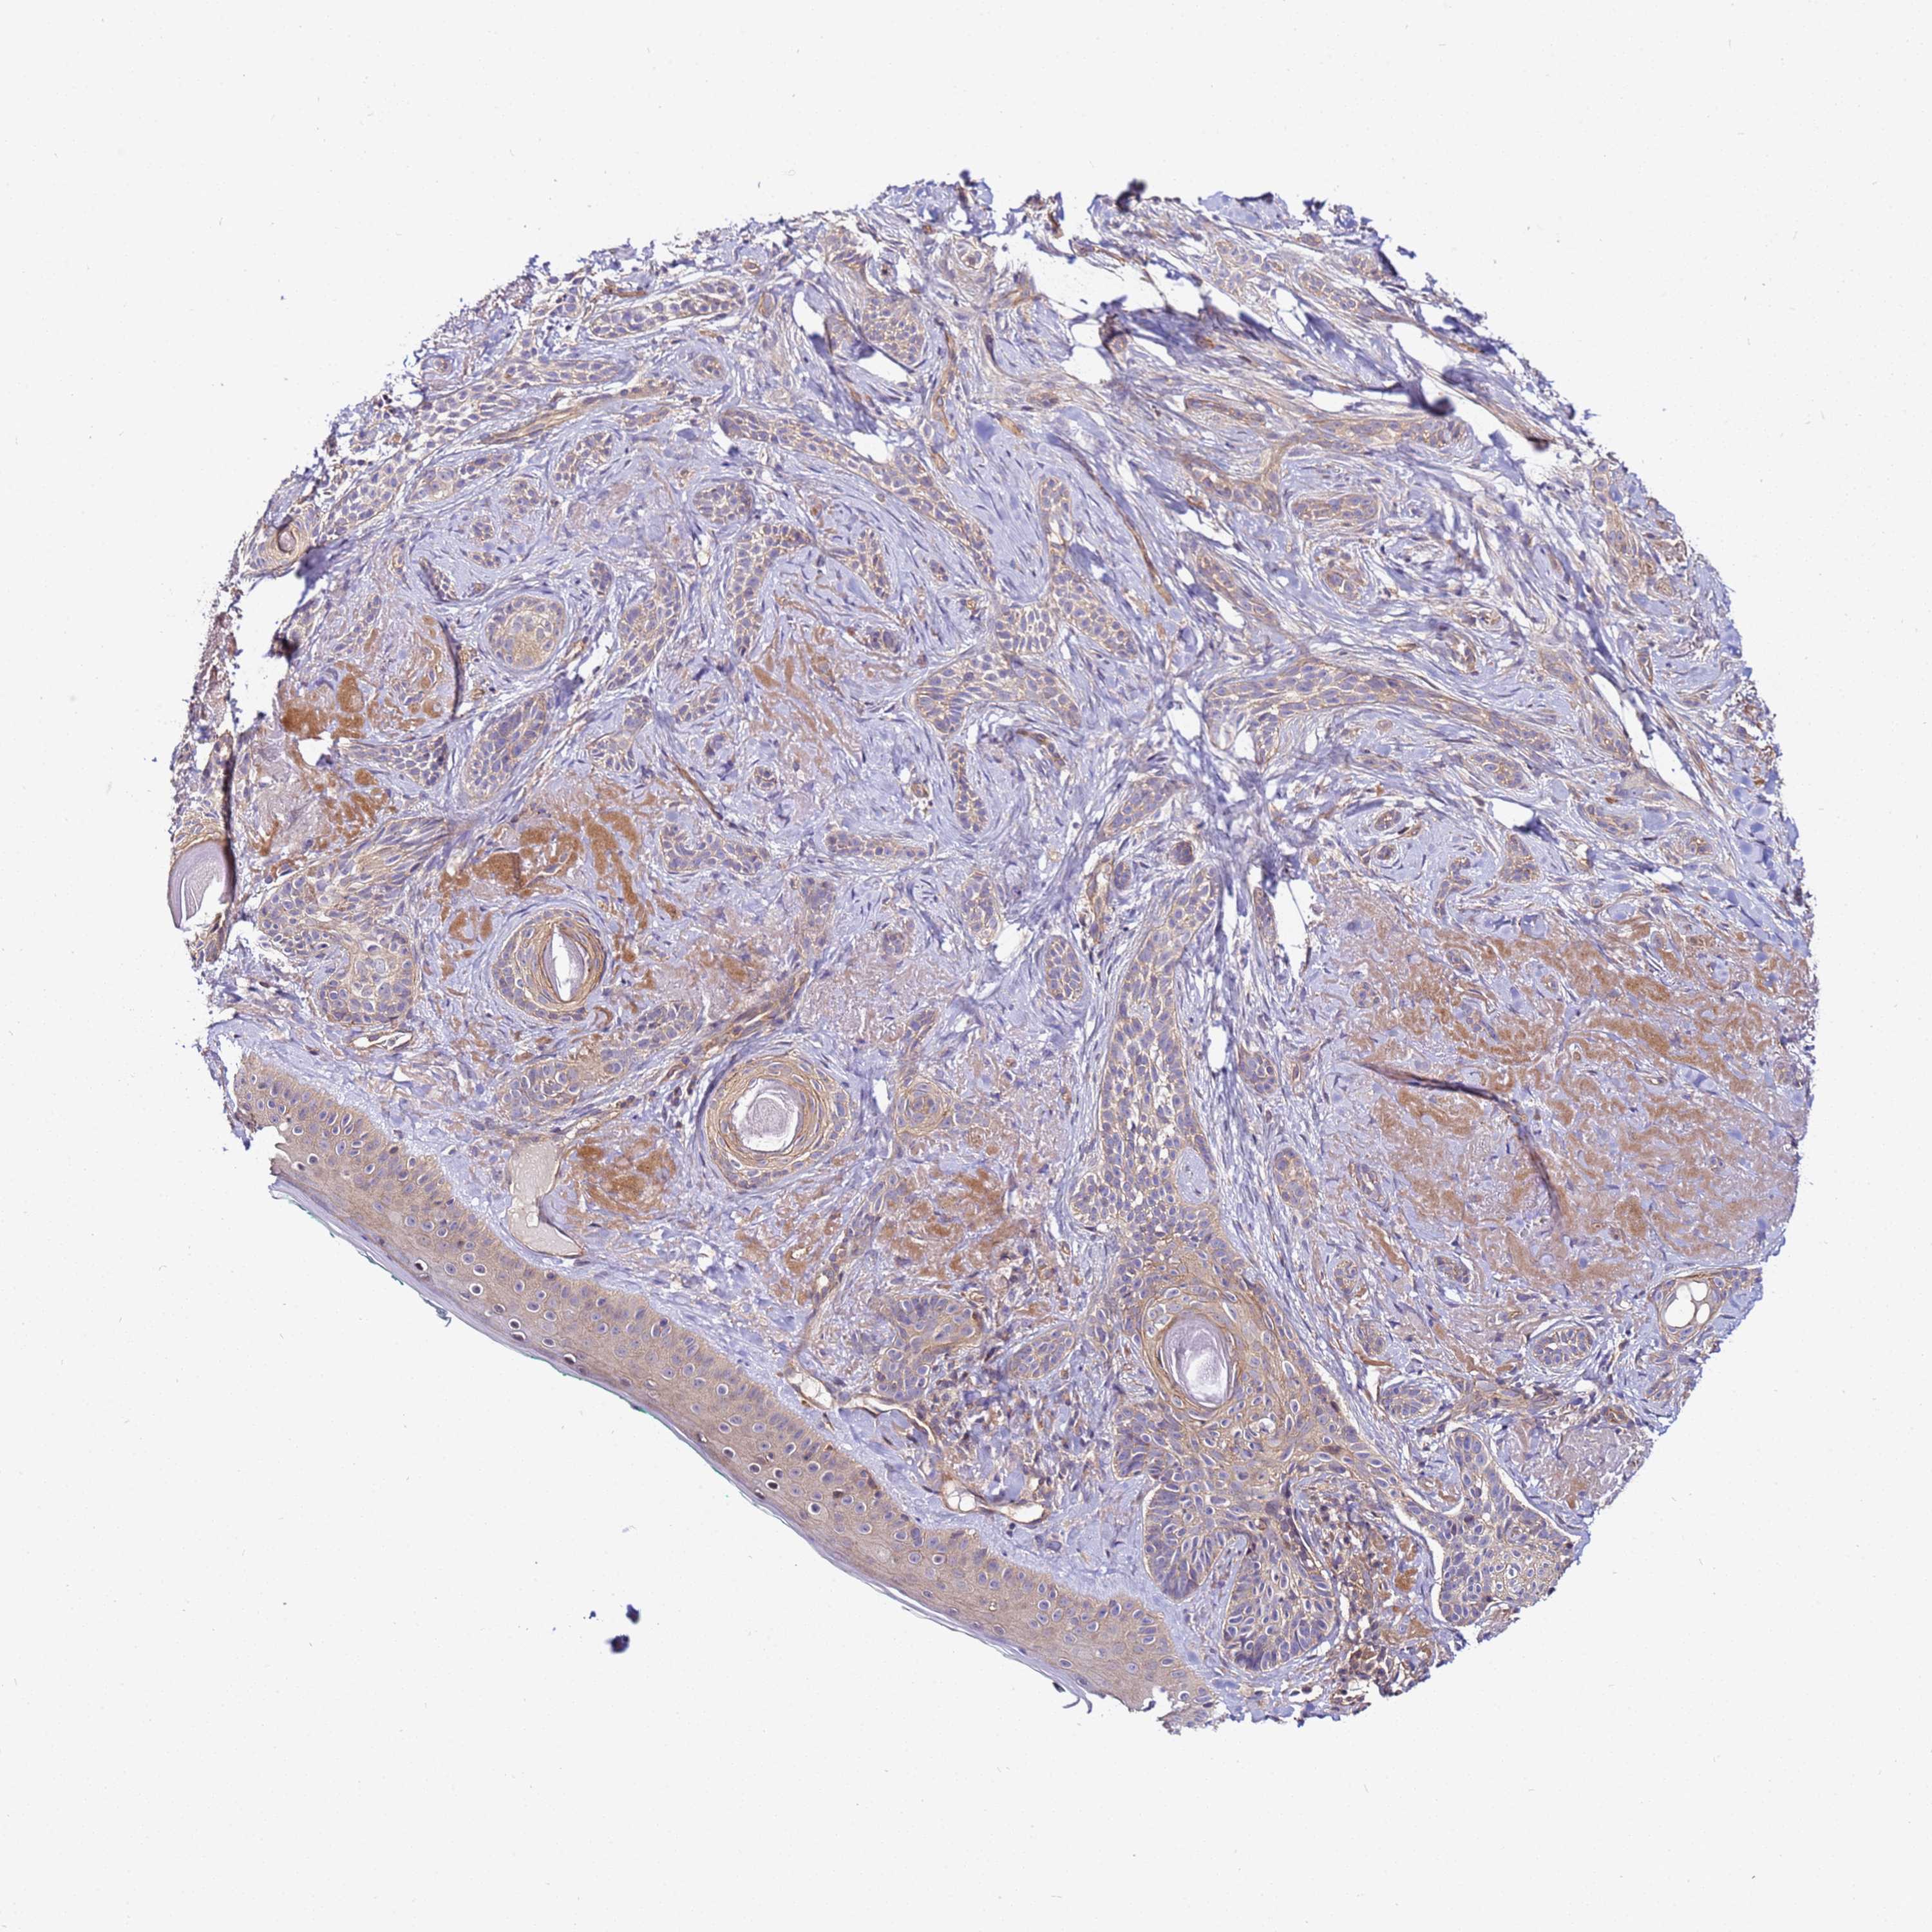

Basal cell and squamous cell cancer

SKIN CANCER - Protein expressioni

A mouse-over function shows sample information and annotation data. Click on an image to view it in a full screen mode. Samples can be filtered based on level of antibody staining by selecting one or several of the following categories: high, medium, low and not detected. The assay and annotation is described here.

Each image is clickable and will lead to virtual microscopy that enables deeper exploration of all samples and also displays staining intensity scores, fraction scores and subcellular localization as well as patient and tissue information for each sample.

Antibody HPA038623

Staining

High

Medium

Low

Not detected

Intensity

Strong

Moderate

Weak

Negative

Quantity

>75%

75%-25%

<25%

None

Location

Nuclear

Cytoplasmic/membranous

Cytoplasmic/membranous,nuclear

Basal cell carcinoma